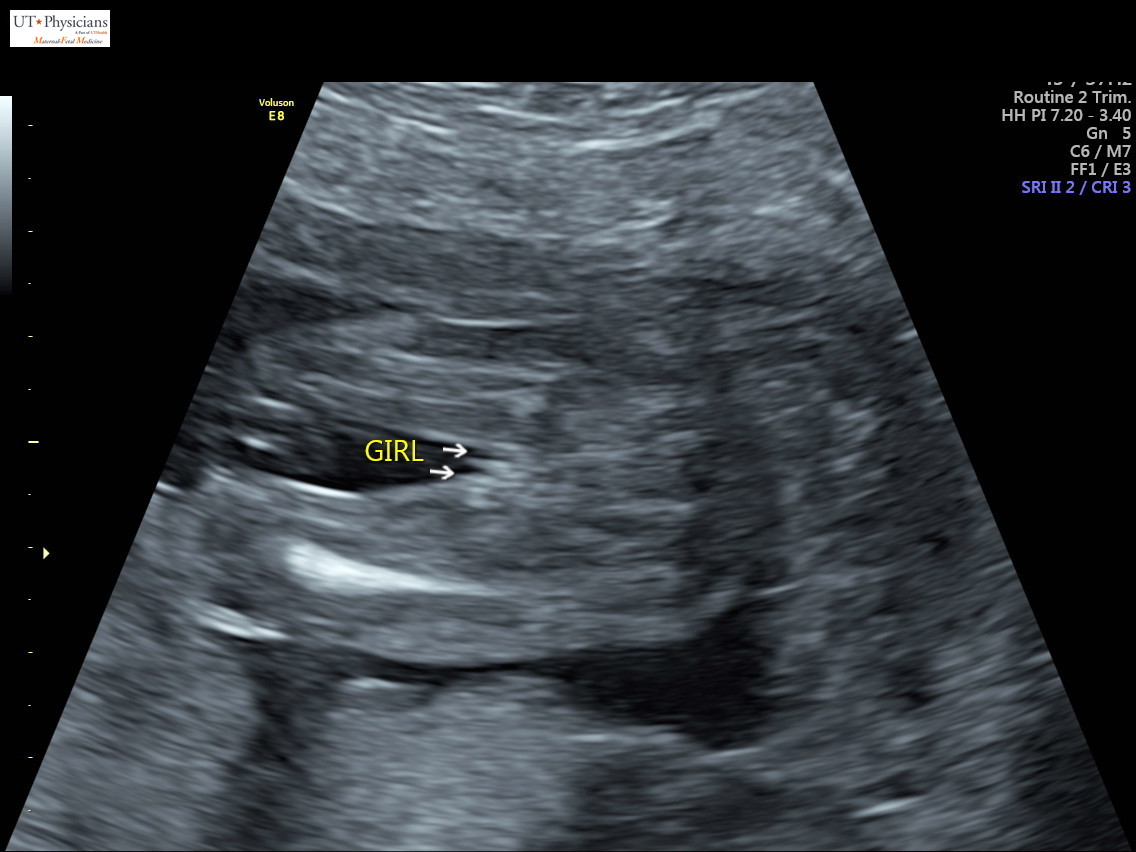

I AM SO FREAKING HAPPY FOR YOU SHENANIGANS! This has been such a long road, I know, but I am just absolutely thrilled you have your pink rainbow. :heart: